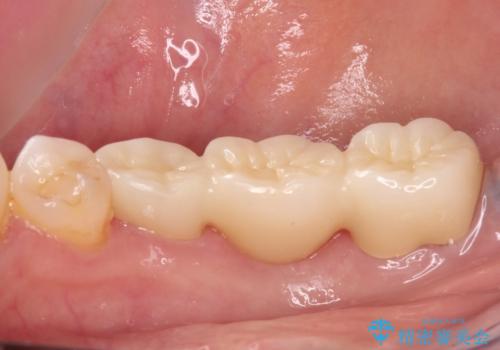

ただし、インプラント以外にブリッジでの補綴治療も可能であったので、抜歯後に治癒を待って、フルジルコニアブリッジにて補綴することとしました。

インプラント治療が回避でき、前後の銀歯も合わせてセラミックにできたので、患者様には大変満足していただきました。